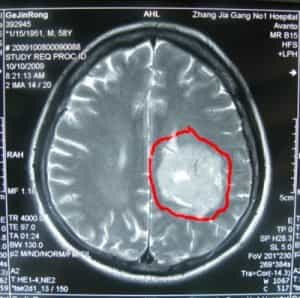

تم إدخال المريض جينغونغ غي، وهو مريض ذكر يبلغ من العمر 59 عامًا من الصين، إلى مستشفى بكين بوهوا الدولي (BPIH) في الصين في 20 أكتوبر 2009، مصابًا بورم سحائي غير نمطي في منطقة مثلثة.

قبل ستة عشر شهرًا من دخوله المستشفى بسبب ورم سحائي غير نمطي في المنطقة المثلثية اليسرى، بدأ السيد جي يشعر بضعف في مرونة ساقه اليمنى، وكأنه يعاني من ضعف في حركتها. لم يسعَ للعلاج فورًا. مرت ستة أشهر، وتفاقمت الأعراض تدريجيًا، مما أثر على مشيته، وكان لصعوبة تحريك ساقه اليمنى أثر سلبي واضح على حياته. ذهب إلى مستشفى محلي وأجرى تصويرًا بالرنين المغناطيسي للدماغ، والذي أظهر وجود ورم في المنطقة المثلثية من البطين الجانبي الأيسر. نُصِحَ بالتدخل الجراحي. رغبةً منه في الخضوع لجراحة الأعصاب لعلاج هذا الورم السحائي غير النمطي، تم إدخال المريض جينرونغ جي إلى مستشفى بكين الدولي للأمراض النفسية.

فحص بالأشعة قبل الجراحة